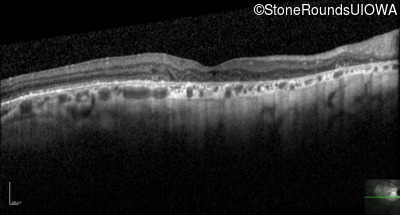

Optical Coherence Tomography - Right - 20/100 +1

Exemplar / OCT Stack